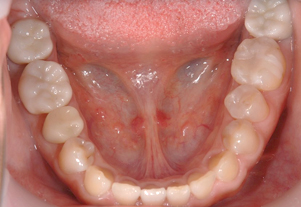

Before

After

ジルコニアクラウン

金属と同じ強度を持ち、生体親和性の高い

安全かつ美しさを兼ね備えた素材です。

人工ダイアモンドと呼ばれるジルコニアは、金属を使用していないため金属アレルギーをお持ちの方でも安心してご使用いただけます。従来の金属に比べ約1/3の軽さで自然な噛み心地を体感していただけます。